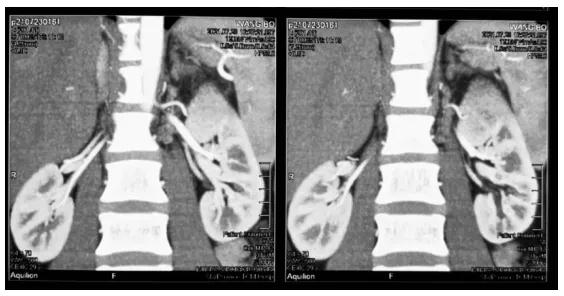

近日,陕西省中医医院泌尿外科成功切除一例巨型肾肿瘤,肿瘤大小6cm*5cm*5cm。

来自延安市吴起县31岁的王先生在体检中发现左肾巨大占位,转辗到多家三甲医院就诊,接诊医生均认为肿瘤巨大,即使行切除肾脏手术,也是手术风险大、死亡率高,而想保住肾脏就难上加难。巨大肾肿瘤保肾手术一直是一个临床难题,肿瘤残留与肾脏丢失,二者往往会使医生和患者很难抉择。

患者经过多方打听,抱着一线希望来陕西省中医医院找张旭主任医师就诊。凭借精湛的技术和丰富的临床经验,张旭主任医师仔细研究患者病情和身体条件后指出肿瘤位置局限于上极,且包膜完整,肾部分切除术能将肿瘤切除并且不影响剩余肾脏的功能,能使患者利益最大化,而且患者很年轻,社会及家庭责任重大。

面对占据肾脏近一半体积的巨大肾脏肿瘤,经过一系列积极而又全面的准备,手术在紧张的氛围中有条不紊的进行。术中发现这位患者肾肿瘤几乎占据整个左侧肾脏上极,血供异常丰富,肾蒂显露困难,这对手术造成了不小的难度。

张旭主任团队凭借丰富的临床经验、娴熟的手术技巧和过硬的心理素质,将肿瘤血供依次切断,清楚暴露好输尿管及肾蒂血管,成功将肿瘤完整剜除。手术操作如行云流水、一气呵成,有惊无险。肾动脉阻断时间为12分钟(原则上不超过半小时)。同时特别感谢麻醉科于军主任、冯文广医生制定及实施精准的麻醉方案,患者在手术结束十分钟内恢复自主呼吸和意识。还有手术室人员的积极配合,为手术的成功奠定了坚实的基础。